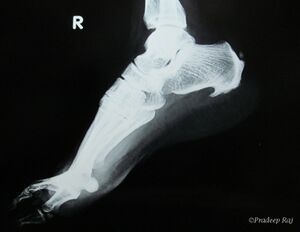

صورة بالأشعة توضح نبتة عظمية على الجوانب الخلفية والسفلية من العقب

مهماز العقب (إنگليزية: calcaneal spur، يُعرف أيضاً باسم مهماز الكعب إنگليزية: heel spur)، هو نتوء عظمي ينمو من عظام الكعب.[1] عادة ما يكتشف مهماز العقب بالأشعة السينية.[2] وهو يشكل العرن.

المهماز العقبي الخلفي يقع على الجانب الخلفي للعقب وهو استجابة طبيعية لالتهاب اللفافة الأخمصية على مدار الوقت، لكنه يرتبط أيضاً بالتهاب الفقار المقسط (عادة لدى الأطفال). يتطور المهماز العقبي الخلفي على ظهر الكعب عند مدخل وتر أخيل.[3]

المهماز العقبي السفلي هو تكلس في العقب، الذي يقع أعلى اللفافة الأخمصية عند مدخل اللفافة الأخمصية. غالباً ما يكون المهماز العقبي الخلفي كبياً وملموساً من خلال الجلد وقد يحتاج إلى إزالته كجزء من علاج التهاب وتر أخيل.[3]

يمكن الكشف عن مهماز العقب بالفحص البدني متبعاً بإجراء الأشعة السينية جانبية للقدم.[بحاجة لمصدر]